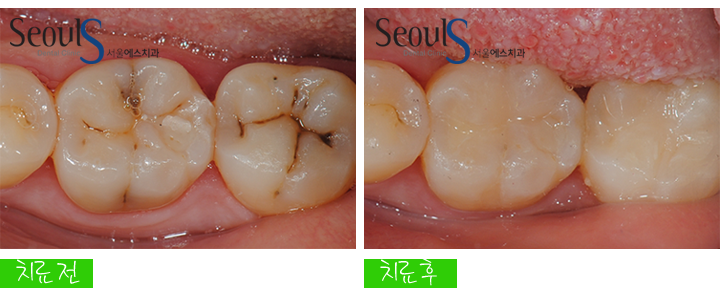

충치 제거 후 치아색으로 때웠습니다

어떤가요?

예쁘게 치료가 마무리 된 모습이죠^^

치료 전후 모습입니다

치아 골을 따라서 충치가 진행 되었는데

충치 제거 후 CAD/CAM 인레이로 때워 치료를 마쳤습니다